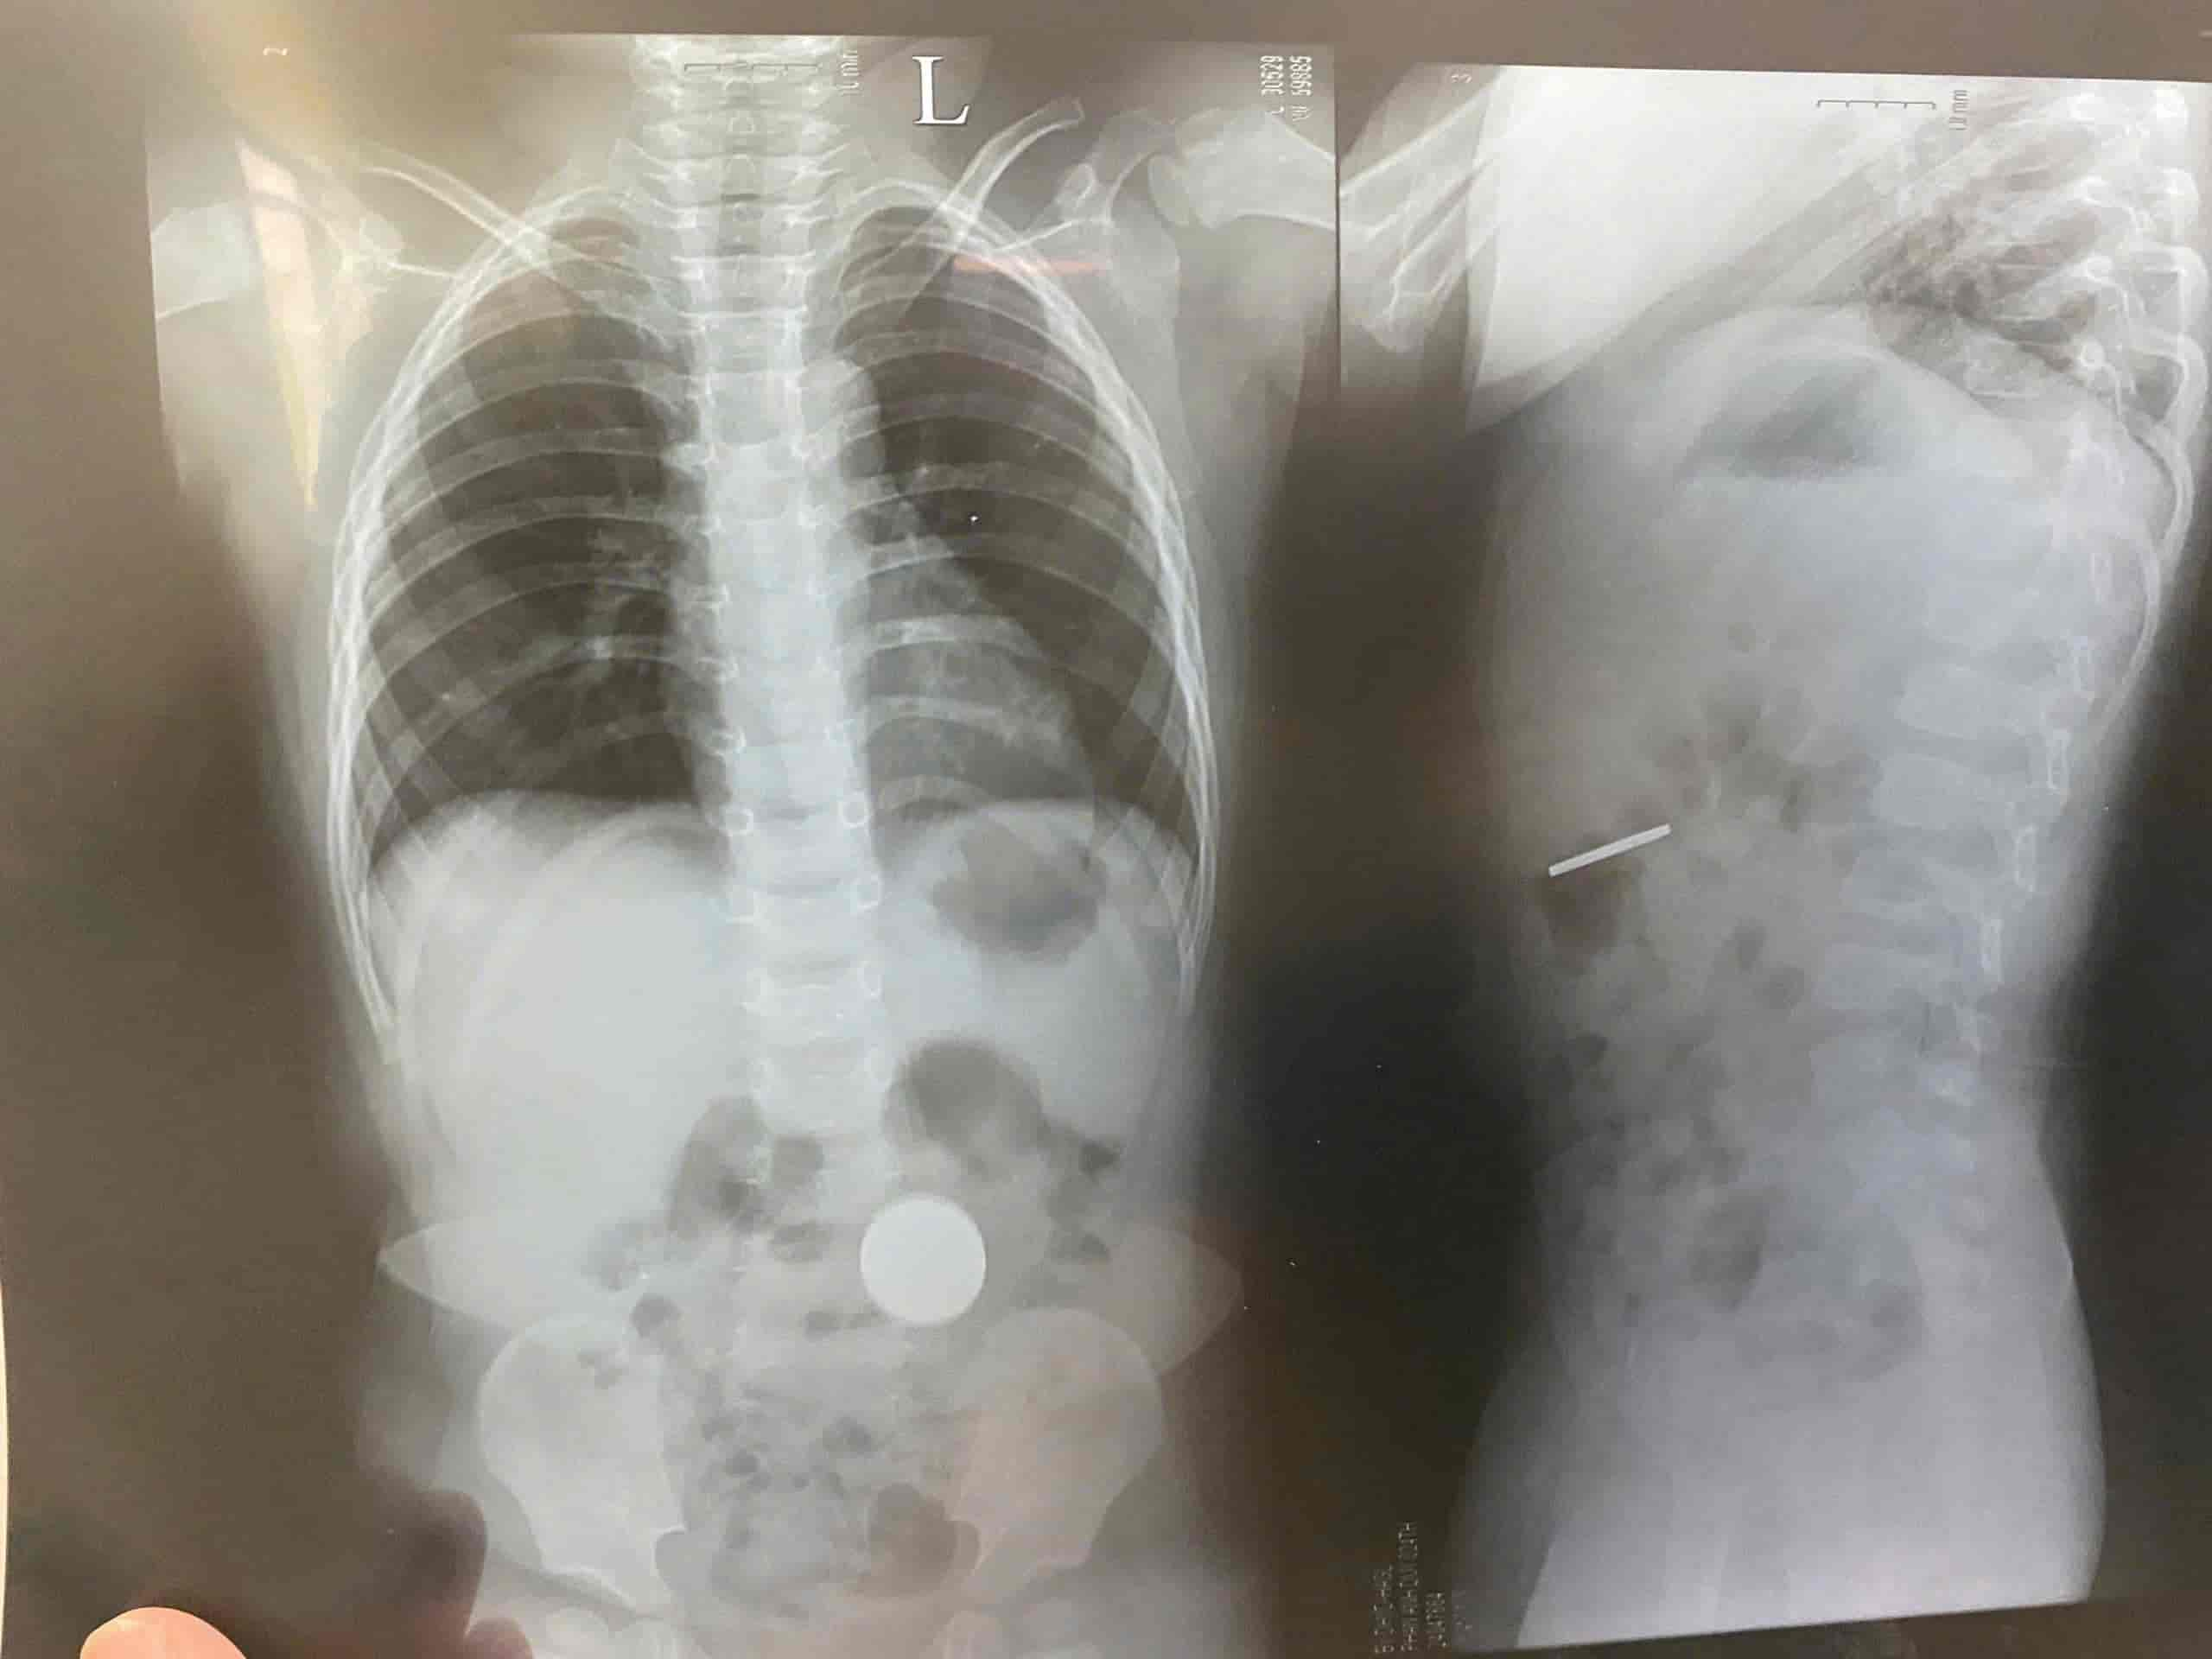

About 3 days later, the child showed symptoms of a lot of coughing and was taken to the doctor. When taking a chest X-ray to check for pneumonia, the doctor discovered a quarter of a third of a foot in the stomach.